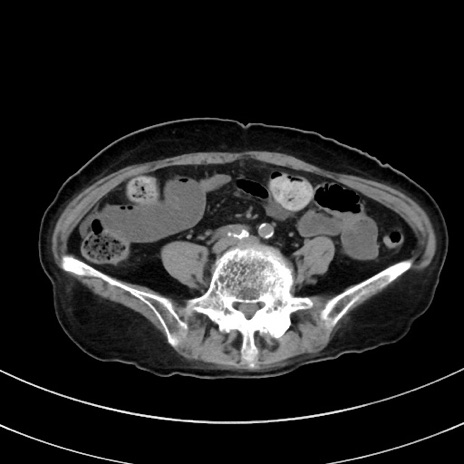

症例33(横断像)

【症例】70歳代 女性

【主訴】心窩部痛

【現病歴】延髄病変の精査・加療にて神経内科入院中。本日より心窩部痛あり。

【身体所見】右下腹部を中心に圧痛と反跳痛あり。

【データ】WBC 10900、CRP 0.02

冠状断像